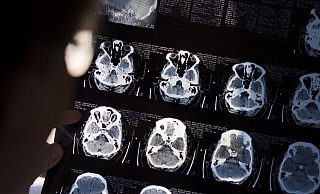

Schlaganfall-Info-Tour in Minden-Lübbecke: Jeder fünfte Untersuchte stark gefährdet

Die 20. Schlaganfall-Info-Tour geht zu Ende. Rund 300 Menschen wurden untersucht. Die Scheu davor, ein Risikoprofil erstellen zu lassen, sei unbegründet.